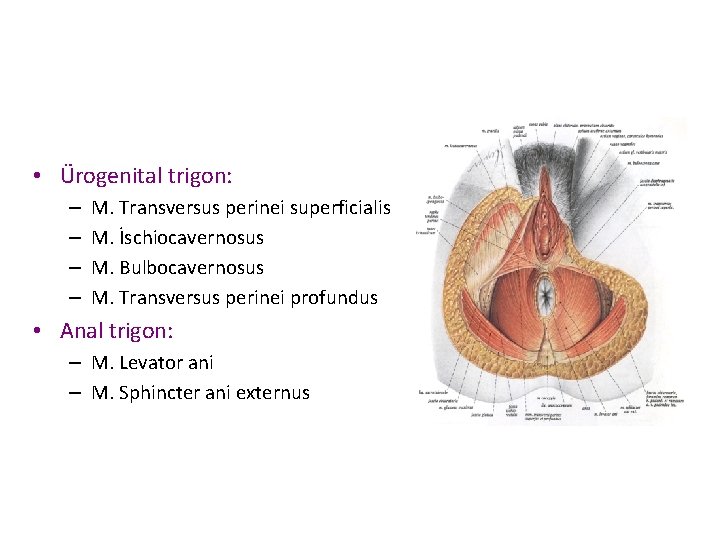

• Ürogenital trigon: – – M. Transversus perinei superficialis M. İschiocavernosus M. Bulbocavernosus M. Transversus perinei profundus • Anal trigon: – M. Levator ani – M. Sphincter ani externus

FIGURE 7. 2. Superficial compartment and perineal membrane.